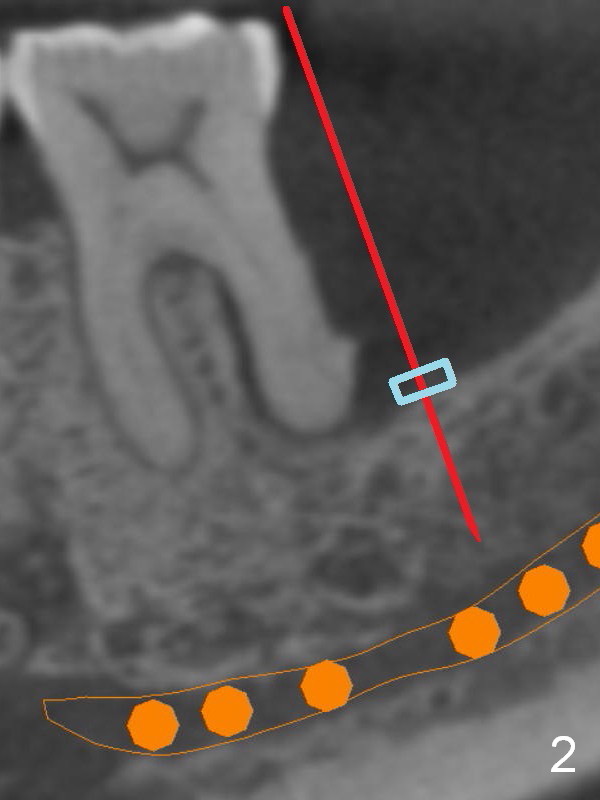

There is severe bone resorption around the distal root of the lower left 1st molar of the 56-year-old man (WG), while the loss of the 2nd molar is associated with limited bone height (Fig.1). A 5x14 mm implant will be placed at the mesial socket of #19 and 5.9 or 6.4x6 mm one is at the mesial site of #18 (Fig.7-9). Use a 2 mm pilot drill with 6 mm stopper from Sinus Master Kit (with extension) to initiate osteotomy at #18 immediately distal to the crown of #19, parallel to the long axis of the latter (Fig.2). After inserting a parallel pin at #18, extract the tooth #19 (Fig.3, antibiotic pending) and start osteotomy with a 2 mm pilot drill with 14 mm stopper (Fig.4). Insert the calibrated parallel pin at #19 (Fig.5) and measure the distance between the two parallel pins (approximately 10 mm, Fig.7). Sequential osteotomy and application of the Tatum taps (Fig.6 red rectangle) will push the septum distal (green arrow). As to #18 osteotomy, trephine, final and tap drills are to be used with control of the depth: 6 mm (Fig.7,9).